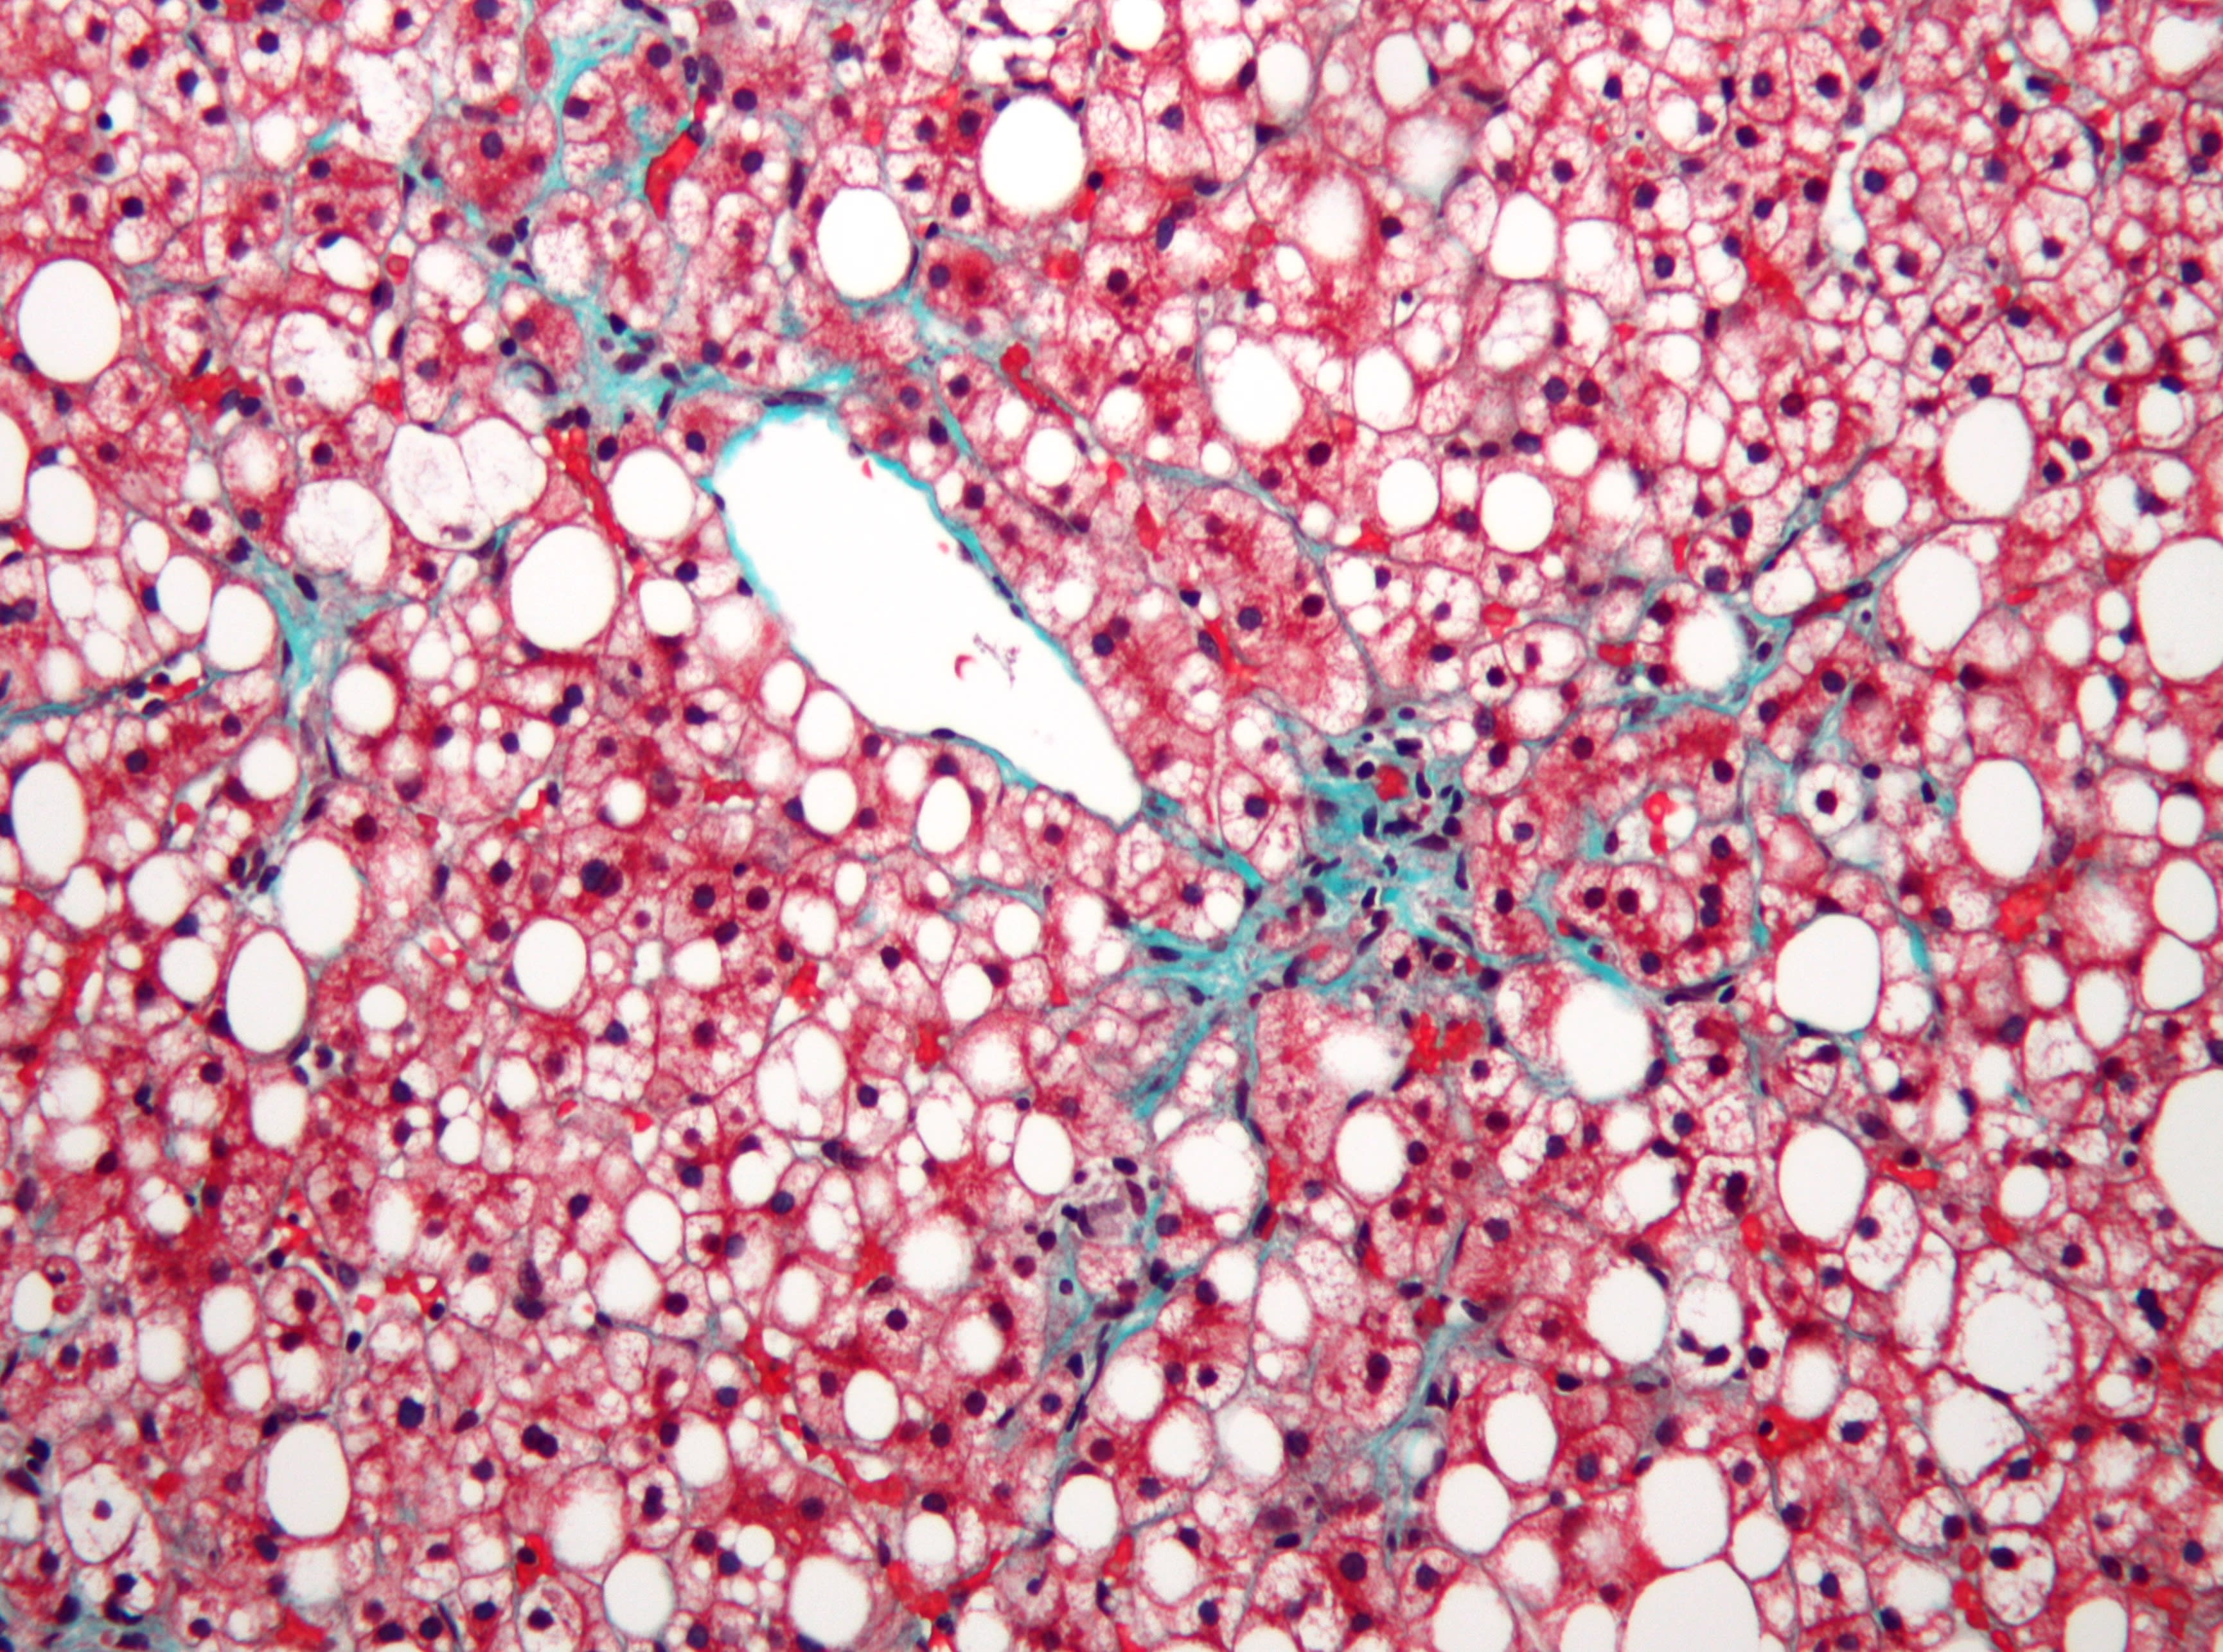

Dorothy was swarmed with gloved hands. The surgeons lifted her liver out and plopped it into a bucket. It clearly looked diseased — engorged, lumpy, and mottled. Without her liver, the cavity of her body looked completely empty, just like John’s had. The two livers rested side-by-side in their respective tubs, John’s bloodless and gray, hers, misshapen and hard, and I thought how strange this exchange of life was.

Dorothy’s diseased liver wasn’t yet at the end of its own journey. A trained staff member carried it in a big bucket from the operating room to the pathology lab. There, it would be “fixed” in formalin, making it rubbery, easy to slice, and safer to manipulate without transmitting viruses. The pathologists would take little sections of it, covering each with special wax, shaving it, and staining it pink and purple to highlight its terrain.

Eventually, the in-house liver pathologist will look at Dorothy’s samples through her microscope. She will, as she puts it, “appreciate what disease this liver has to show.”